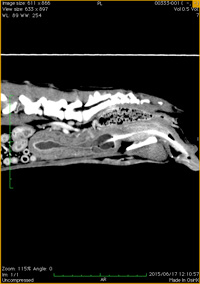

猫の鼻腔腺癌

椎間板ヘルニア

直腸腺癌と骨盤転移

巨大な肝臓腫瘤

膀胱−尿道移行上皮癌

尿道移行上皮癌